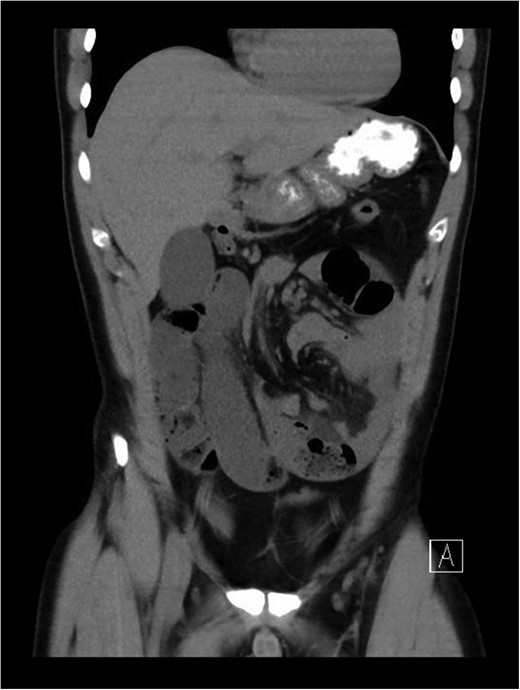

Coronal view of CT abdomen and pelvis revealing incarcerated internal hernia with signs of small bowel obstruction, whirl sign suggestive of volvulus.

The patient presented to a local hospital at approximately mid-day with worsening severe central abdominal pain associated with vomiting and obstipation. The symptoms had been rapidly progressing over a period of 12 h. He finally presented with pain preventing him from lying flat. Patient had no history of abdominal surgery, trauma or large food bolus. There was no other relevant past personal or family history. On examination, he appeared diaphoretic and in distress, but maintained normal vital signs, except for bradycardia. His examination revealed signs of florid peritonism, with rigid distended abdomen. Initial blood films were only remarkable for hypophosphatemia (0.33 mmol/L) with a normal lactate (1.1 mmol/L) and pH (7.30 with base excess of −3 mmol/L). His white cell count was 11.8 × 109, and had a C-reactive protein of 14. An abdominal computed tomography (CT) scan was performed and revealed features highly suggestive of mid-gut volvulus with associated obstruction and likely vascular compromise (Figs 1 and 2).

X-rays and CT imaging may help in identifying signs of obstruction, volvulus and/or strangulation in patients with internal hernias [8]. Certain CT features represented by clustering of dilated small bowel peripherally without overlying Omentum and leading to colonic displacement centrally may be suggestive of transmesenteric hernias [8]. However, final diagnosis will only be confidently achieved intraoperatively [3, 9]. In our case, CT findings were suggestive of bowel obstruction with mid-gut volvulus to be the likely cause.